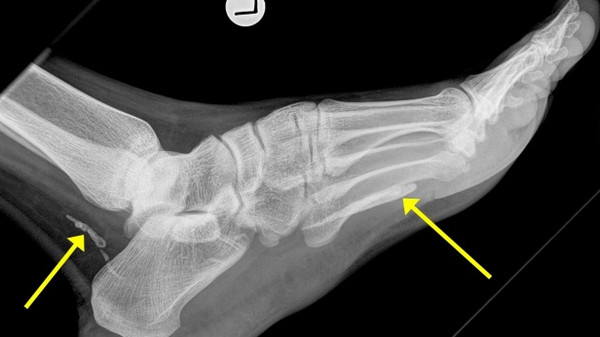

▲「龍線蟲」寄生於澳洲男子腳踝中,導致腳踝腫脹。(圖/翻攝自澳洲《The Age》)

澳洲東岸城市墨爾本(Melbourne)一名38歲從蘇丹移民來的男子因腳痛就醫,醫生透過X光片,意外發現他的腳踝中有疑似為「龍線蟲」的寄生蟲,且已經死亡腐爛,才會導致腫脹疼痛的狀況。在經過手術後,醫生已經將腳踝中的寄生蟲取出,男子也已經全面康復。

根據澳洲《The Age》報導,澳洲St Vincent's醫院的醫生達比(Jonathan Darby)指出,這名受感染的男子已經移民到澳洲將近4年,經過判斷,「龍線蟲」已經生活在他的腳下多年,所幸透過X光發現,腳踝內分成兩部分的寄生蟲只有幾公分長,男子也在手術後恢復健康。